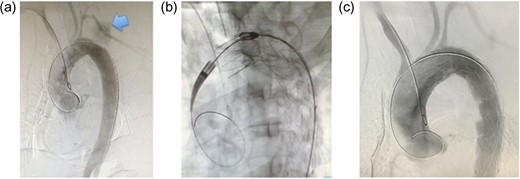

(a) Intraoperative aortography. Extravasation of contrast medium is observed (arrow). Additionally, the site of rupture could be precisely identified. (b) Intraoperative aortography. With the common femoral artery approach, stent grafts are placed between just distal to the left common carotid artery and the distal aortic arch. To achieve sufficient length of the proximal landing zone, the left subclavian artery is covered intentionally. (c) Postoperative aortography. Extravasation of contrast medium is not seen and there is no endoleak.